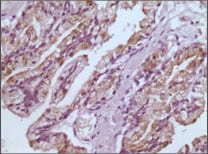

- Immunohistochemical analysis of paraffin-embedded human prostate tissues using GSTP1 mouse mAb with DAB staining.